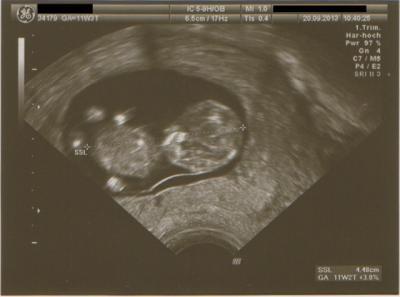

Kürmel ist quick lebendig. Hat ganz schön getobt da drin ;-) Meine Tochter hatte damals beim US immer geschlafen. Alles scheint richtig entwickelt zu sein. Mein Mann durfte heute mitkommen und auch Krümel kucken Anbei noch ein Bildchen

Bild zu FA Termin bei mir auch supi :) - Forum für April - Mamis